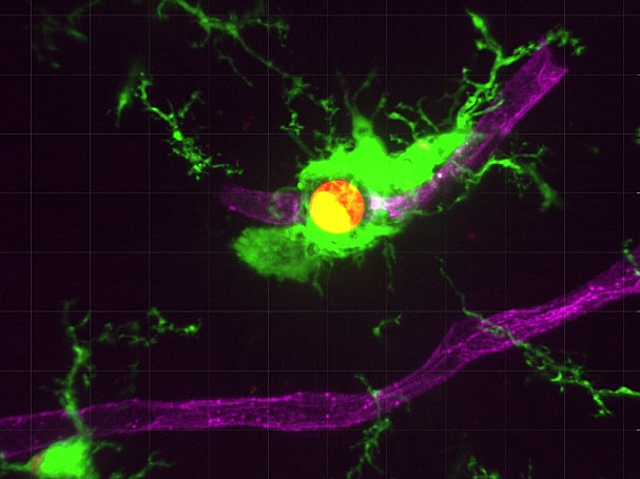

Igual que una persona de la neteja que, davant una queixa per un vessament, es limita a amagar-lo davall de l’estora, les cèl·lules immunitàries del cervell semblen oferir una solució incompleta davant algunes infeccions fúngiques. Els investigadors van estudiar com les microglies de ratolí, les cèl·lules immunitàries residents del cervell, responen a la infecció per Cryptococcus neoformans, un fong que pot causar una meningitis mortal. Van observar que estes cèl·lules detecten el fong dins dels vasos sanguinis abans que travesse la barrera hematoencefàlica, que protegix el cervell. Els fragments alliberats per la càpsula del fong són captats per les cèl·lules que recobreixen els vasos sanguinis, les quals donen l’alarma i demanen ajuda. Les microglies (verd) envolten els vasos sanguinis (rosa) i engoleixen els fongs (roig), però no aconseguixen eliminar-los completament i, fins i tot, poden proporcionar-los un entorn ric en nutrients que afavorix la seua proliferació. Comprendre i, finalment, manipular esta interacció podria conduir a noves estratègies per a tractar o previndre les infeccions fúngiques cerebrals

Imatge del treball de Chenxu Feng, Ge Wang i Yixuan Wang, i col·laboradors/es

Sheng Yushou Center of Cell Biology and Immunology, School of Life Sciences and Biotechnology, Shanghai Jiao Tong University, Shanghai, Xina